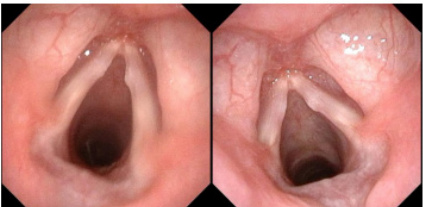

治疗后,两组患儿声带息肉体积均减小,声带闭合间隙变小,且对照组改善程度更明显。

图3- 1 电子喉镜检查结果显示观察组休声后息肉体积较前期减小

图 3- 2 电子喉镜检查结果显示对照组训练后声带息肉体积较前期

减小

图3- 3 电子喉镜检查结果显示对照组较观察组声带闭合间隙更小